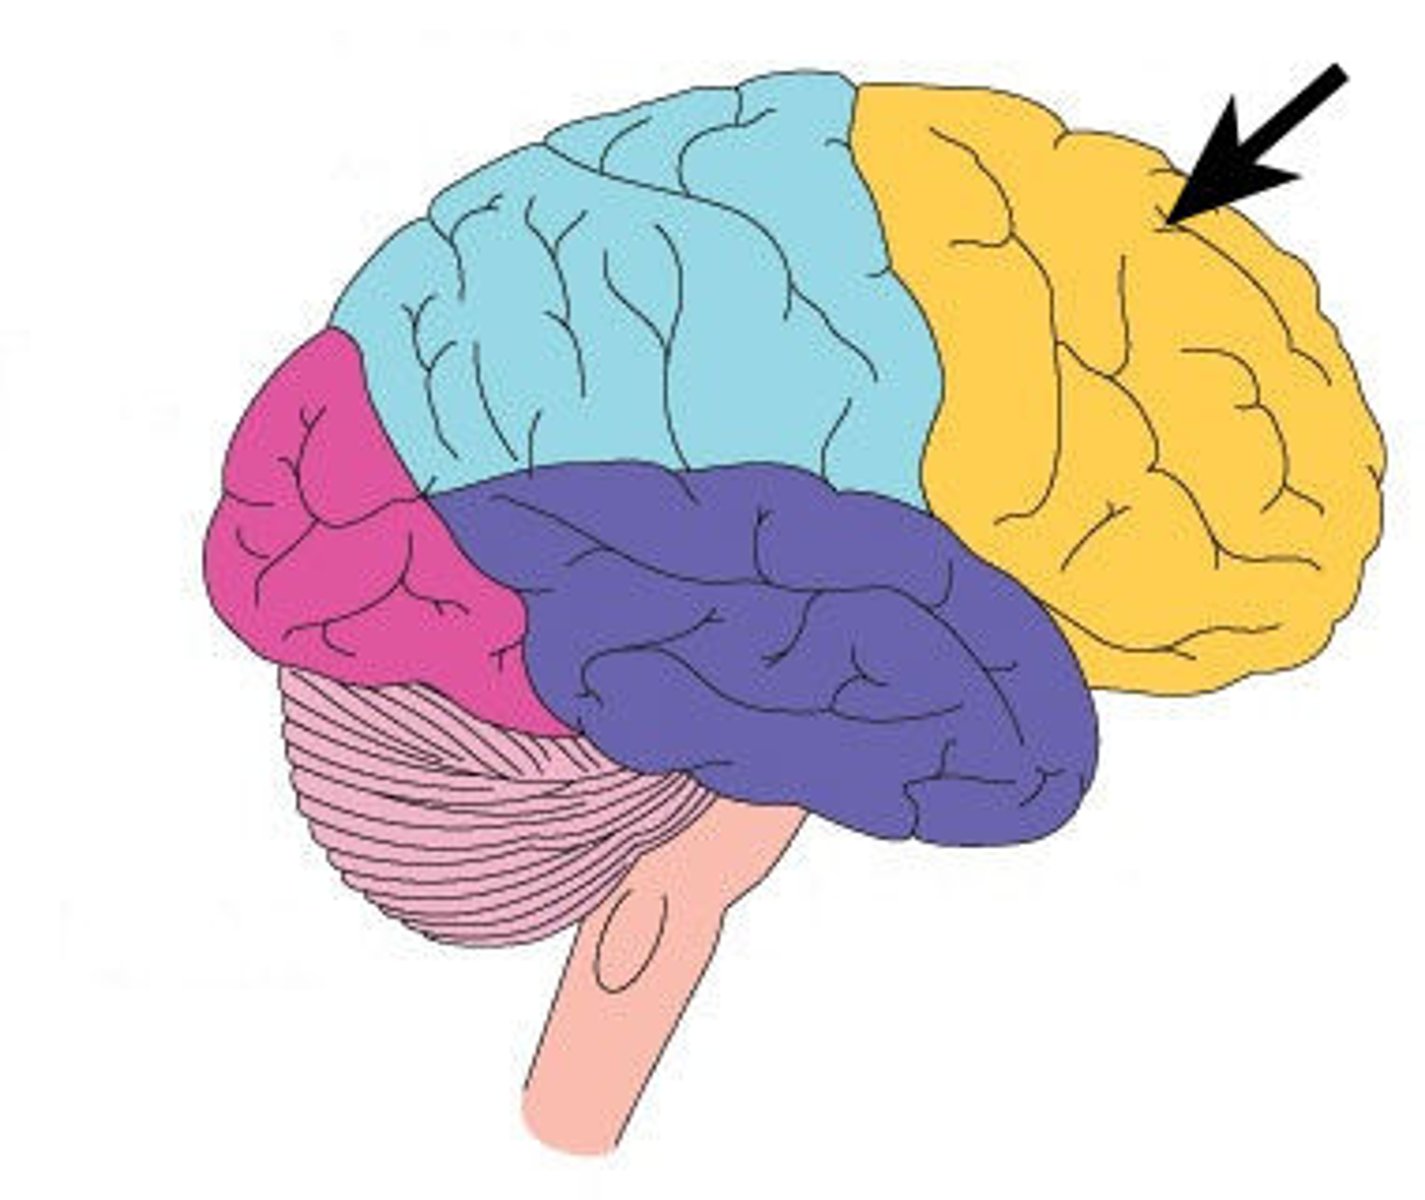

frontal lobe

associated with social cues, personality, planning, movement, emotions, and problem solving - contains primary motor cortex

precentral gyrus

primary motor cortex

parietal lobe

A region of the cerebral cortex whose functions include processing information about touch, contains primary somatosensory cortex

postcentral gyrus

primary somatosensory cortex

occipital lobe

visual center

temporal lobe

language centers, auditory processing, olfactory

central sulcus

between postcentral and precentral gyri

longitudinal fissure

separates cerebral hemispheres

transverse fissure

separates cerebrum from cerebellum